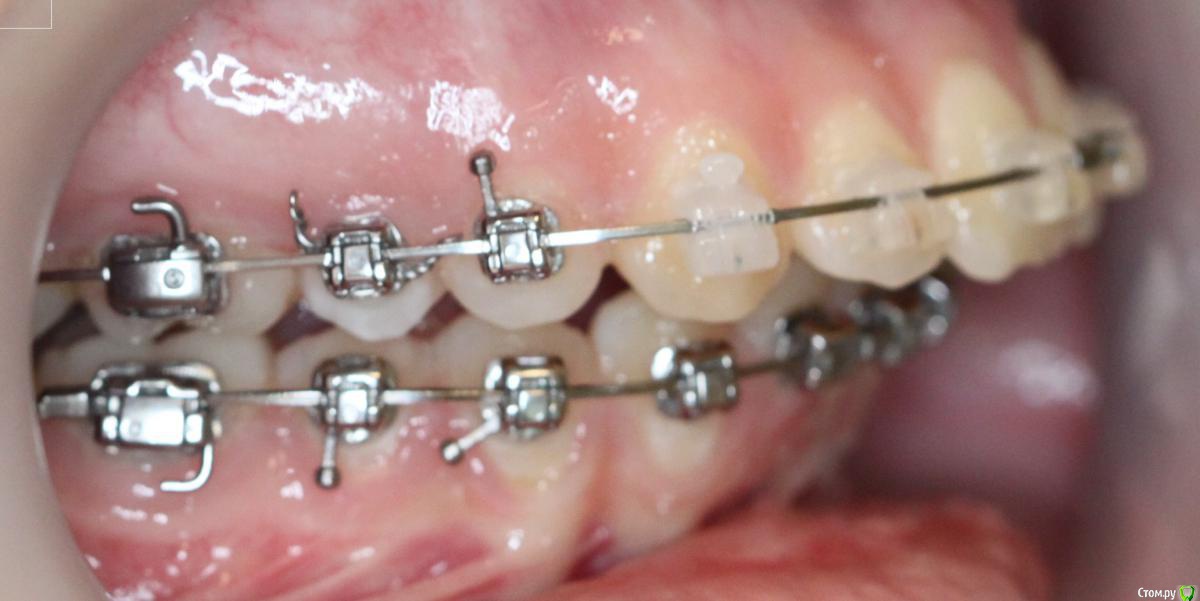

annurka Опубликовано 12 сентября, 2017 Поделиться Опубликовано 12 сентября, 2017 (изменено) здравствуйте! 24 года, дисфункция ВНЧС, дистальный прикус (1,4см), ортодонтическое лечение начато с ношения каппы для разгрузки сустава (привыкла подтягивать НЧ к верхней) в 2012 году. проведено лечение: удаление всех 8к (непрорезавшиеся), расширение ВЧ (аппарат дерихсвайлера), выравнивание зубных рядов, сепарация нижних резцов (резцы были наклонены), места не хватило - удаление 2 нижних 4к, выравнивание кривой шпее, двухчелюстная остеотомия; выравнивание окклюзионных контактов (резиновые тяги) проблема: между верхними и нижними резцами расстояние 5мм к трг (внизу фото) есть расшифровка.все идет к снятию брекетов, и с эстетической точки зрения меня все устраивает. но не до конца устраивает в функциональном плане (я не могу пропихнуть палец между зубными рядами, как раньше, но все также подтягиваю челюсть кпереди когда ем, говорю)стараюсь контролировать это, но даже улыбнуться не могу не подтянув - иначе у меня некрасиво вырисовывается подбородок, неправильно произношу звуки при разговоре.сразу после остеотомии состыковка резцов была ок - нижние зубы были за верхними, но мы с ортодонтом занялись состыковкой и других зубов (которые тогда не соприкасались), и когда добились контактов жующих сторон, разошлись резцы.UPD: и еще есть черные треугольники на НЧ - с ними тоже очень хочется разобраться лечащий ортодонт говорит, что это в целом норма, с учетом моего случая. и возможно это так, но я очень хочу послушать еще мнений, возможно стоит удалить 2 зуба наверху, чтобы верхняя челюсть подошла по размер нижней? [боюсь что простой сепарации может не хватить и как в случае с нижними резцами придется и сепарацию делать, и удалять зубы.] может быть еще есть другой способ добиться нормального прикуса, без "нюансов"?изначально я пошла на все это лечение, чтобы остановить разрушение сустава (однажды проснулась и не смогла рот даже открыть, еще до лечения), полагала, что брекеты и члх исправят если не ситуацию, то причину, но я все еще двигаю НЧ вперед к ВЧ. с остеотомии прошел почти год (поэтому на изменение картины эластиками я уже не надеюсь), брекеты ношу почти 4 года. заранее всем спасибо за отклик! Изменено 12 сентября, 2017 пользователем annurka 1 Ссылка на комментарий

annurka Опубликовано 13 сентября, 2017 Автор Поделиться Опубликовано 13 сентября, 2017 (изменено) А До лечения есть ТРГ посмотреть? И фото какие-нибудь?есть трг сверху - сразу после остеотомии, снизу - через полгода после (когда резцы отошли друг от друга на 5мм) до лечения вообще точно делал ортодонт (снимки, слепки, фото), если в клинике это сохранили, я смогу сфотографировать. далее фото в процессе лечения - 4ки нижние еще не удалены, один хирург был готов так оперировать, другой сказал, что наклон нижних резцов неправильный и нужно как и было запланировано удалить 4ки, сепарации недостаточно.челюсть расслаблена как есть: НЧ подвинута к ВЧ для наглядности: есть фото слепков того периода, но форум ругается на слишком большой размер. если нужно - уменьшу залью) Изменено 13 сентября, 2017 пользователем annurka 1 Ссылка на комментарий

annurka Опубликовано 14 сентября, 2017 Автор Поделиться Опубликовано 14 сентября, 2017 (изменено) Нет, я трг пока не могу рассчитать, чтобы это утверждать - на выходных только время будет, а пока с телефона смотрю. Предполагаю,да.Ну и плюс контакты зубы ищут правильные и смыкаются в разном положениивообще к обоим трг (до и нынешнее) я добавила расшифровку выше, или вы имеете ввиду те, что с титановыми конструкциями? мне все же хочется верить что это с зубами беда, и они новой челюсти не подходят, а не то что челюсть куда-то съехала.. в принципе, как и любому человеку, пережившему перемещение двух челюстей. еще есть такое фото, сделала его сразу после операции, швы не позволяли толком губы раскрыть, а рот нельзя было открывать на протяжении месяца, поэтому такое качество: http://i12.pixs.ru/thumbs/5/6/2/w1BZH71BWi_3410341_27523562.jpghttp://i12.pixs.ru/thumbs/5/5/3/4pJjOEAIq2_4300116_27523553.jpg там видно, что резцы сходятся как следует, а больше никаких контактов нет у других зубов. эластик (который скреплял от движения челюсть) в то же время создавал контакты клыков, носила только их месяца 4. фото через месяц после оп, тенденцию верхних резцов уже видно (но рот мне еще открывать нельзя было)http://i12.pixs.ru/thumbs/6/4/3/IMG5512JPG_8912889_27523643.jpghttp://i12.pixs.ru/thumbs/6/3/1/4pJjOEAIq2_7818185_27523631.jpghttp://i12.pixs.ru/thumbs/6/4/9/IMG5522JPG_8755357_27523649.jpghttp://i12.pixs.ru/thumbs/6/5/1/IMG5525JPG_1306296_27523651.jpg спустя 2 месяца после оп, стала жевать еду, открывать рот могла только на 2смhttp://i12.pixs.ru/thumbs/6/5/7/IMG9072JPG_6555113_27523657.jpghttp://i12.pixs.ru/thumbs/6/6/5/IMG9080JPG_2398494_27523665.jpghttp://i12.pixs.ru/thumbs/6/7/3/IMG9085JPG_1231417_27523673.jpg по ссылке доступно увеличенное изображение, спасибо Skip Изменено 14 сентября, 2017 пользователем annurka Ссылка на комментарий